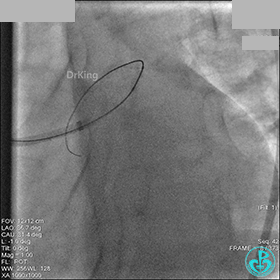

1周后再次上台,右冠脉3级血流,3段局限性严重狭窄,内膜模糊,应该是上次操作夹层遗留下的血肿。

先处理前降支开口严重狭窄并顺利植入前降支到左主干支架。